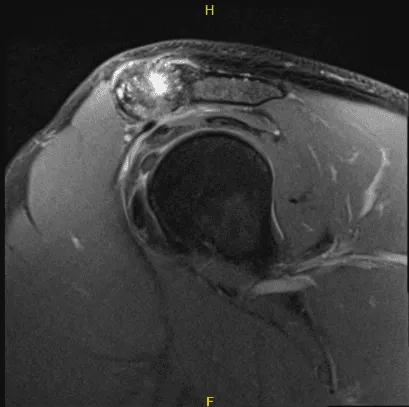

The patient presented an MRI result that showed high-grade partial-thickness articular surface tear at the supraspinatus tendon insertion. Low-grade partial-thickness articular surface tear of the distal infraspinatus tendon. Moderate AC joint arthrosis.

A small subacromial spur predisposes the patient to external impingement. Nondisplaced tear of the posterosuperior labrum. Mild subacromial subdeltoid bursitis.